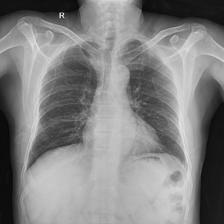

To pre-train a high-performance X-ray foundation model, the first thing we need to do is the collection of large-scale X-ray images. Therefore, a large-scale and high-resolution dataset that contains X-ray medical images is collected for the pre-training. Some representative samples are visualized in Fig. 3.